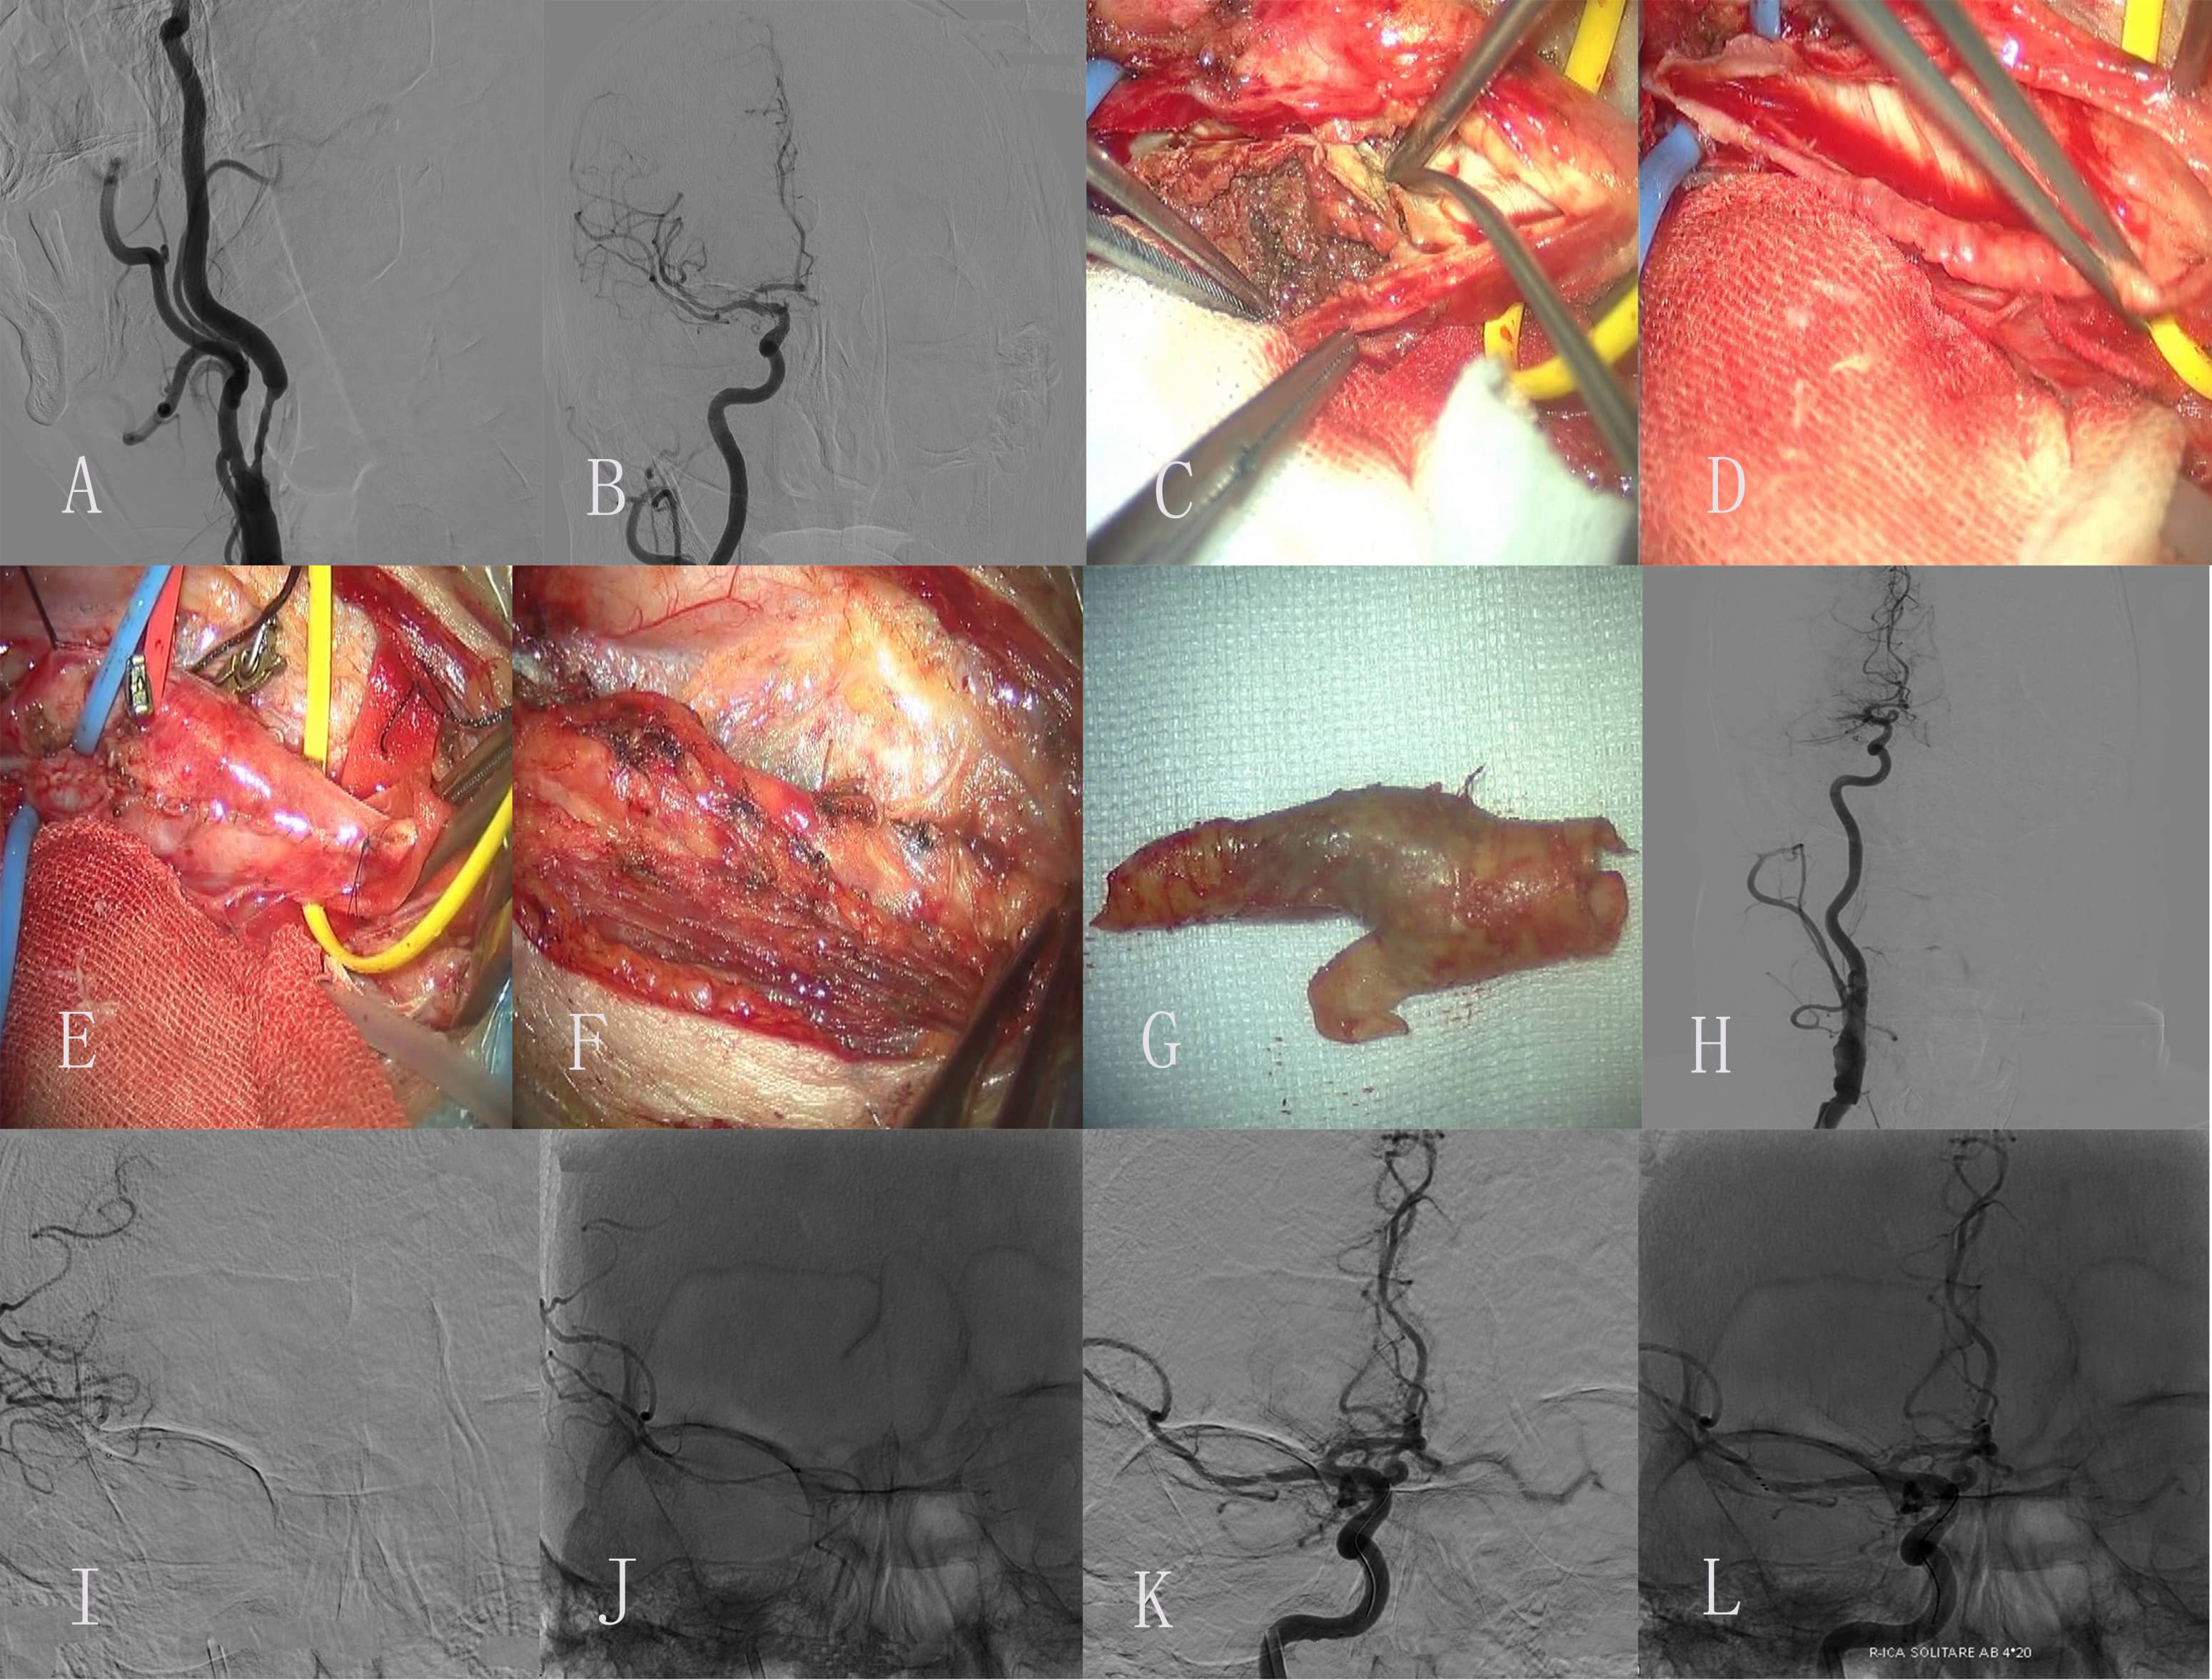

Fig. 1.Images of Case 1. (A) Preoperative right common carotid artery

(CCA) arteriogram revealed a severe proximal internal carotid artery (ICA)

stenosis. (B) Preoperative right middle cerebral artery (CMA) and anterior

cerebral artery (ACA) arteriogram revealed normal. (C) The endometrium of the CCA

was dissected longitudinally and presented as muddy unstable plaques. (D)

Completed removal of plaque. (E) Incision suture. (F) Close the carotid sheath.

(G) Intimal plaque. (H) Postoperative right CCA arteriogram revealed the M1

segment of the right MCA is occluded. (I,J) Superselective angiography of a

microcatheter through an occluded segment reveals a distal image of the occluded

vessel. (K,L) Solitaire 4